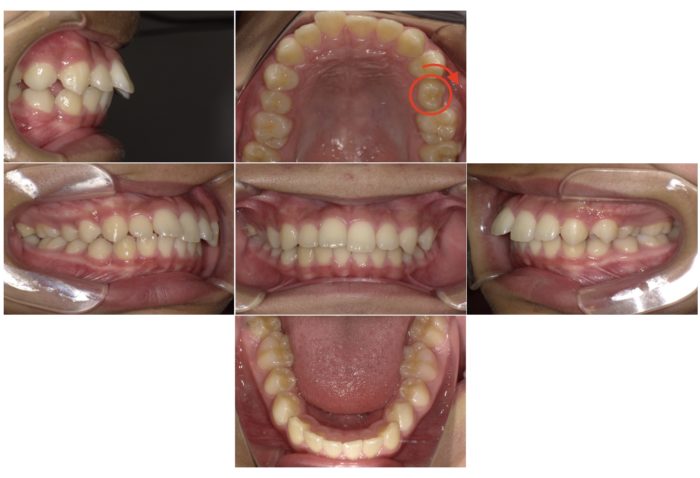

◼︎かみ合わせが悪いと学校の歯科健診で指摘され来院

ご本人もご家族も、これまでかみ合わせの悪さを感じたことはありませんでした。

学校の歯科健診で指摘を受け、近所の歯科医院で矯正相談をされたそうです。

その際、上の歯を2本抜いて矯正する方法を提案されましたが、健康な歯を抜くことに抵抗があり、当院の無料相談(カウンセリング)にお越しいただきました。

歯を抜かずに治せた理由

抜歯をせずにスペースを確保するため、以下の方法を組み合わせています

- 上顎の赤い丸が付いている歯のねじれを改善し、歯の向きを正しくする

- 歯の側面をわずかに削るIPR(ディスキング)でスペースを作る

- 奥歯を後方に移動させて前歯を後退させる

これにより、歯を抜かずに口元の突出感を改善することができました。